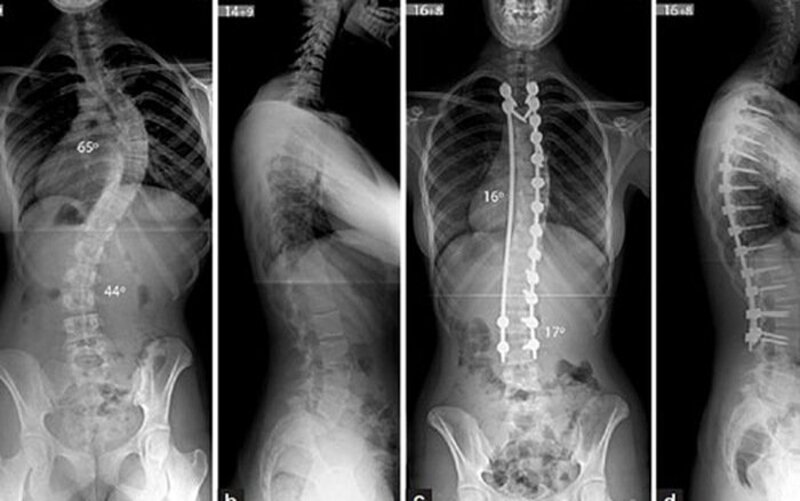

Chụp X-quang: Khi thực hiện kiểm tra này, một lượng nhỏ bức xạ được sử dụng để tạo ra hình ảnh cột sống của người bệnh.

7.3. chữa vẹo cột sống bằng phẫu thuật

Phẫu thuật là lựa chọn của nhiều bệnh nhân với mong muốn sớm cải thiện đường cong cột sống. Tuy nhiên phẫu thuật chỉ là giải pháp cuối cùng khi mức độ vẹo cột sống của bệnh nhân quá nặng và các phương pháp bảo tồn không còn tác dụng